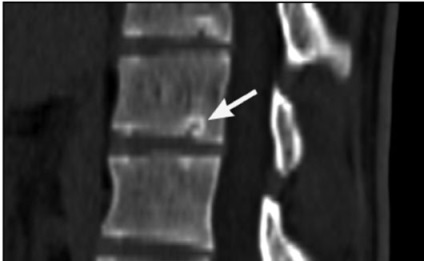

Foto: multiple SHmorlja hernie

Foto: hernia SHmorlja centrală

Diagnosticul se face pe baza:

Metoda principală de diagnosticare a bolii - radiografie, care în acest caz se numește spondylography. Imaginea ei se schimbă în funcție de vârstă.

tomografie computerizata si imagistica prin rezonanta magnetica sunt folosite pentru a confirma diagnosticul.

Simptomele tipice ale unei SHmorlja hernie - defecte uzurativnye.

Acest termen se numește neregularitățile de plăci sau prezența obturator de „buzunare“ specifice, care sunt introduse în corpul vertebral și sunt transparente pentru radiografii.

O hernie copil de 10 de ani arata ca un defect osos care ocupă ¼-o treime din suprafața și înălțimea corpului vertebral, în colțul frontal al vertebrei, marginea care este clar și sclerotic.

Endplates mărginesc Defectul acte ale discului, plinte granița spate.